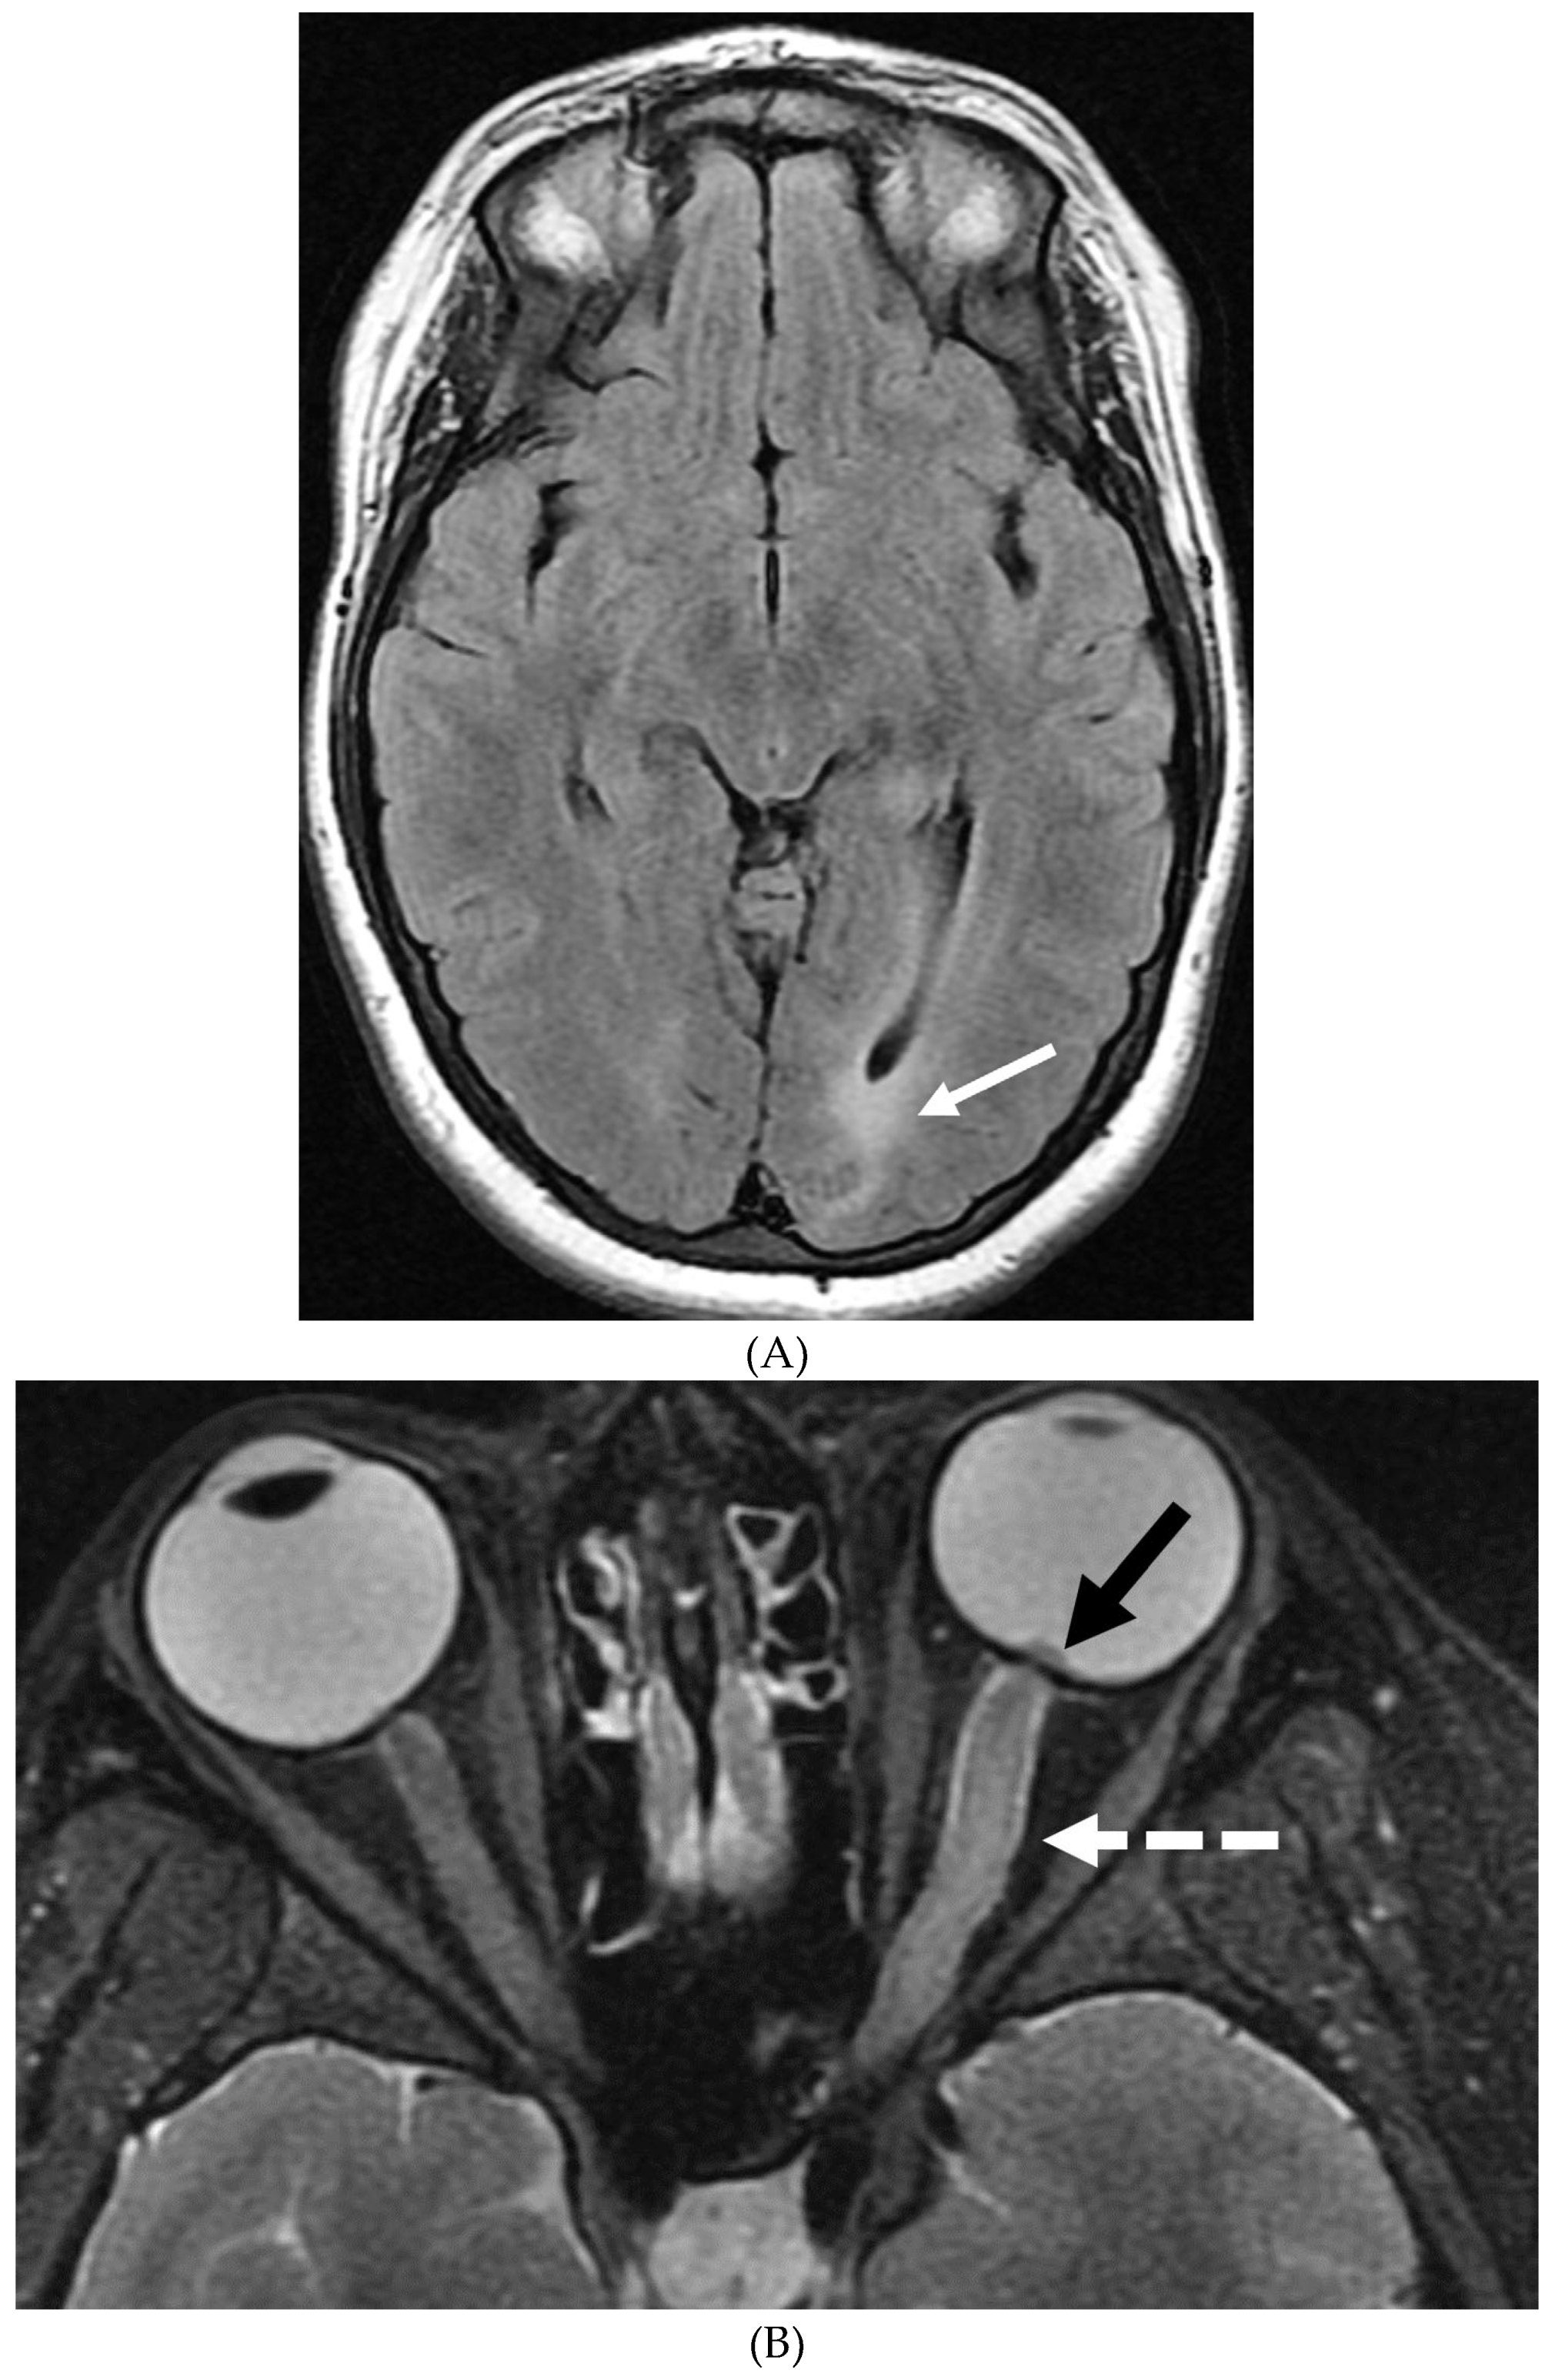

GUILLAIN BARRE SYNDROME

- Alkan O, Yildirim T, Tokmak N, Tan M. Spinal MRI findings of guillain-barré syndrome. J Radiol Case Rep. 2009;3(3):25-8. Epub 2009 Mar 1. PMID: 22470650; PMCID: PMC3303301. [CrossRef]

- Zuccoli G, Panigrahy A, Bailey A, Fitz C. Redefining the Guillain-Barré spectrum in children: neuroimaging findings of cranial nerve involvement. AJNR Am J Neuroradiol. 2011 Apr;32(4):639-42. Epub 2011 Feb 3. PMID: 21292802; PMCID: PMC7965877. [CrossRef]

- Yikilmaz A, Doganay S, Gumus H, Per H, Kumandas S, Coskun A. Magnetic resonance imaging of childhood Guillain-Barre syndrome. Childs Nerv Syst. 2010 Aug;26(8):1103-8. Epub 2010 Jun 17. PMID: 20556395. [CrossRef]

- Byun WM, Park WK, Park BH, Ahn SH, Hwang MS, Chang JC. Guillain-Barré syndrome: MR imaging findings of the spine in eight patients. Radiology. 1998 Jul;208(1):137-41. PMID: 9646804. [CrossRef]

- Malhotra A, Zhang M, Wu X, Jindal S, Durand D, Makhani N. MRI findings of optic pathway involvement in Miller Fisher syndrome in 3 pediatric patients and a review of the literature. J Clin Neurosci. 2017 May;39:63-67. Epub 2017 Feb 10. PMID: 28209311. [CrossRef]